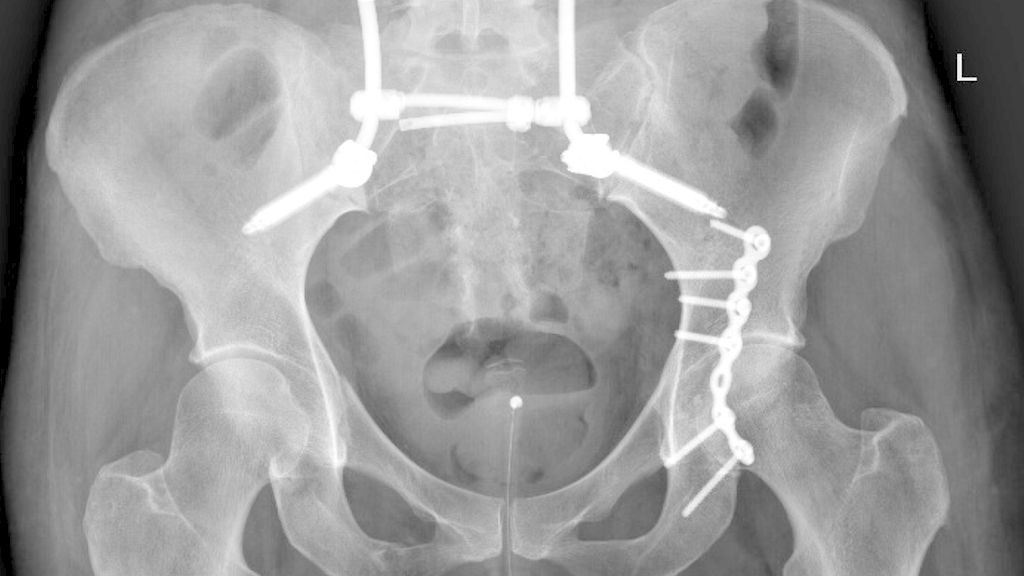

Abb. 1: Beckenübersicht einer 48-jährigen Patientin mit lumbopelviner Stabilisierung und Acetabulumplattenosteosynthese nach Sturz aus großer Höhe mit lumbopelviner Dissoziation und mehrfragmentärer transforamineller Frakturkomponente, oberer und unterer Schambeinastfraktur rechts und Acetabulumfraktur links